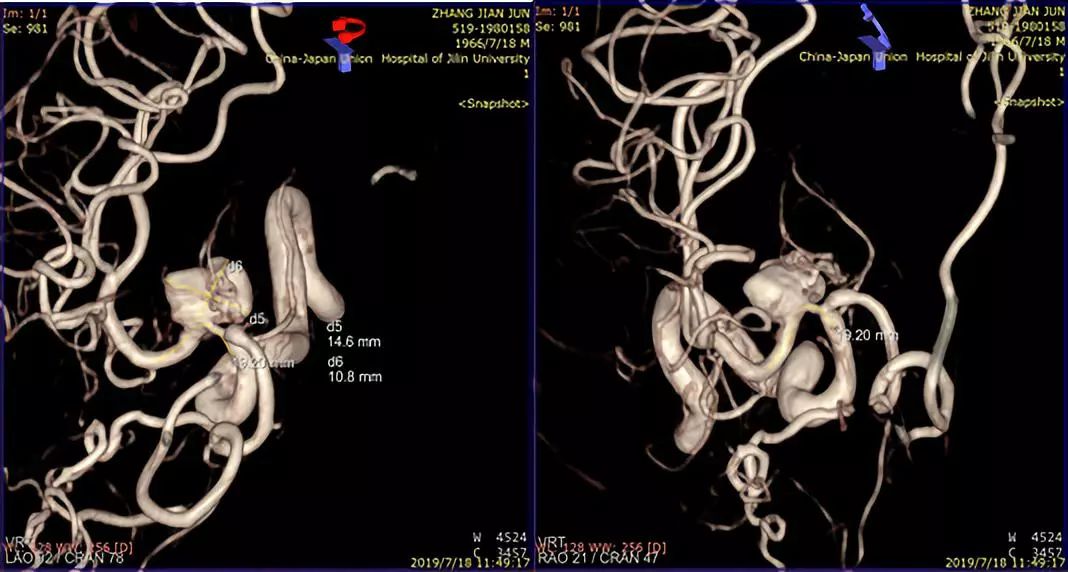

术前造影:

1、造影后显示右侧大脑中动脉M1段动脉瘤,路径图引导下由Traxcess(0.014,200 cm)微导丝携带Marksman支架微导管超选进入右侧大脑中动脉M2段远端(图一)。

此患者为一53岁的男性患者,因发现右侧大脑中动脉M1段动脉瘤2周而住院治疗。从患者影像学资料分析,患者动脉瘤的形态学很不稳定,而且有明显增大的趋势,血流滞留很明显,考虑夹层动脉瘤可能性较大。患者有头痛的病史,对比两周前的影像资料,动脉瘤有增大趋势。患者治疗意愿比较强烈。造影结果显示,患者夹层动脉瘤上方有一较大的分支动脉—豆纹动脉。请神经外科会诊,会诊意见:手术干预难以保留豆纹动脉,开颅手术不具有治疗优势。与患者及患者家属沟通后,患者及患者家属积极要求介入治疗。

术前讨论:如何使患者获得最大受益?因为是夹层动脉瘤,如果填圈治疗,一是外侧豆纹动脉会即刻闭塞,更易引起临床症状;二是填圈治疗有使夹层动脉瘤撕开、出血的风险。所以经讨论我们决定采取一种折中方案,只放密网支架而不填圈的手术方式。我们希望通过密网支架的支撑,使夹层动脉瘤慢慢消失。通过慢性闭塞,给夹层动脉瘤上方的豆纹动脉部位一个代偿血管增生的时间,减少患者发生偏瘫的概率。经过精准测量后,选择合适支架。术中手术顺利,术后进行血管三维重建,密网支架放置良好,贴壁良好,可以清晰的看到豆纹动脉。术后患者回到病房后,一般情况良好。术后18小时后患者出现言语含糊、左侧中枢性面舌瘫,左侧肢体偏瘫,CT排查出血后考虑是患者夹层动脉瘤上方的豆纹动脉闭塞引起的症状。立即行全脑血管造影,发现豆纹动脉确实消失。确定豆纹动脉消失是引起患者临床症状的一个主要原因。这是天坛医院第一例在密网支架植入术后第一天就复查造影的患者。造影结果让我们惊喜的发现,密网支架治疗后,不到18个小时,患者的动脉瘤几乎完全消失。从而证明,我们的手术通过精准测量,选择合适的密网支架对夹层动脉瘤的治疗效果以及夹层的修复效果是非常明显的。当然,患者出现穿支动脉的闭塞,是我们术前充分考虑的,且无法避免的一个并发症。术后给予神经康复,高压氧治疗,患者有明显的好转趋势。我们希望通过后续的康复治疗可以使患者的生活接近正常,同时我们也在密切随访患者,希望患者动脉瘤完全消失,并且正常生活。